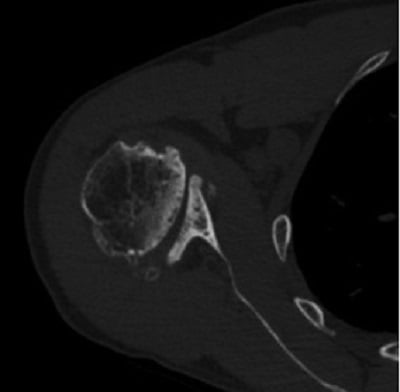

Radiographs of the right shoulder showed end-stage glenohumeral osteoarthritis with significant glenoid retroversion (B3 Walch classification) [1] and posterior humeral head subluxation (Fig. 1). A computed tomography (CT) scan to assist with preoperative planning showed excessive glenoid wear, with 25° of retroversion (Fig. 2).

Figure 2: Axial CT image demonstrates 25° of glenoid retroversion.